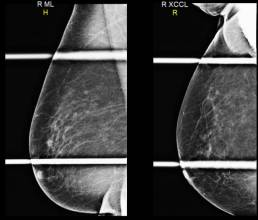

Case of the Week (week 42, 2021)

74 year old female with a family of breast cancer in two maternal aunts (age 80’s).

Screening mammogram: new small spiculated, 0.6 cm mass in the right upper outer quadrant, which persisted on spot compression views. MammoScreen: Soft tissue lesion noted on both the CC and MLO views with a score of 6. Ultrasound: 0.6 x 0.5 x 0.7 cm vascular mass. Shear wave elastography: The lesion is soft which lowers the level of concern. Ultrasound guided core biopsy: Micro invasive carcinoma with DCIS; ER/PR + Her2 -. Ki-67 moderate 11%.

*Case from Weinstein Imaging Associates, Danielle Sharek, M.D.